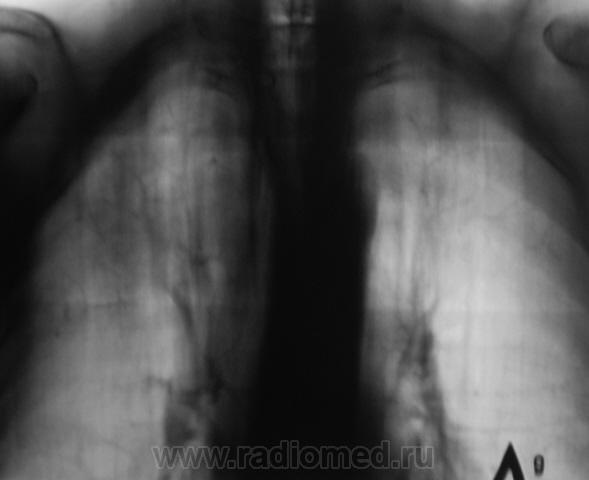

И откуда он берется? Очередной контроль после флюорографии.

Контроль передвижного флюорографа.

Сегодня дообследовали.

да тубркулеза у Вас хватает!

Не оказался "пневмонией". Сегодня пришел коллега фтизиатр записать изображения на диск, посылает пациента в ОПТД, палки найдены.